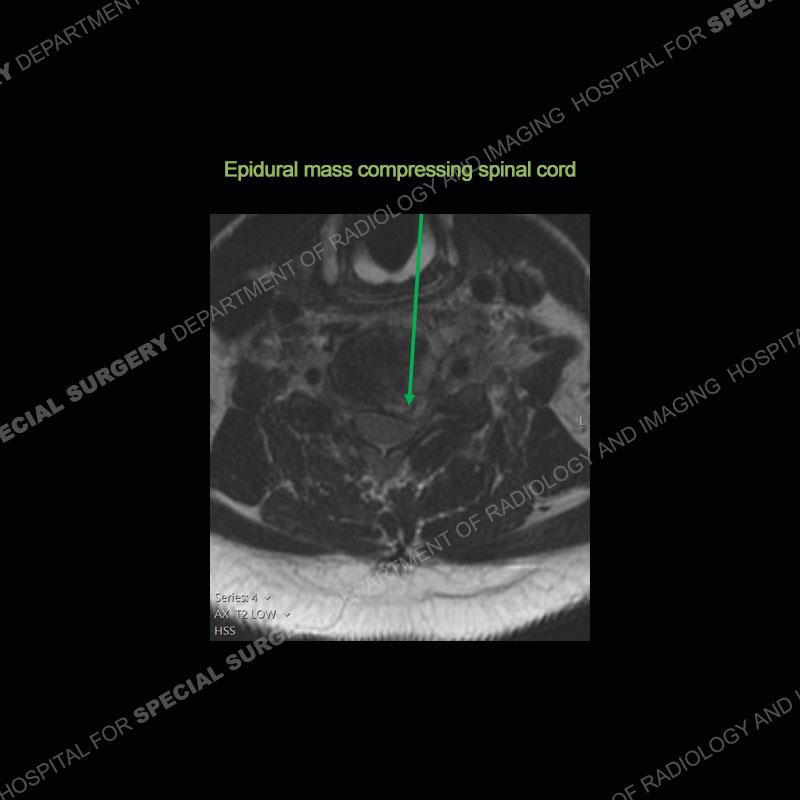

The radiographs demonstrate a prevertebral soft tissue fullness centered at C5-C6 that persists even on extension. There is a slight loss of disc height at C5-C6. The CT more readily shows the prevertebral soft tissue swelling at C5C6 where there is a punctate focus of gas. On the MRI, there is a marked amount of edema and a heterogeneous collection in the prevertebral soft tissue at C5-C6. Edema is present of the C5 and C6 vertebral bodies with a loss of the normal architecture about the disc space. A heterogeneous epidural collection has formed that causes compression of the spinal cord asymmetric to the left side and also precipitates severe left sided neural foraminal stenosis.